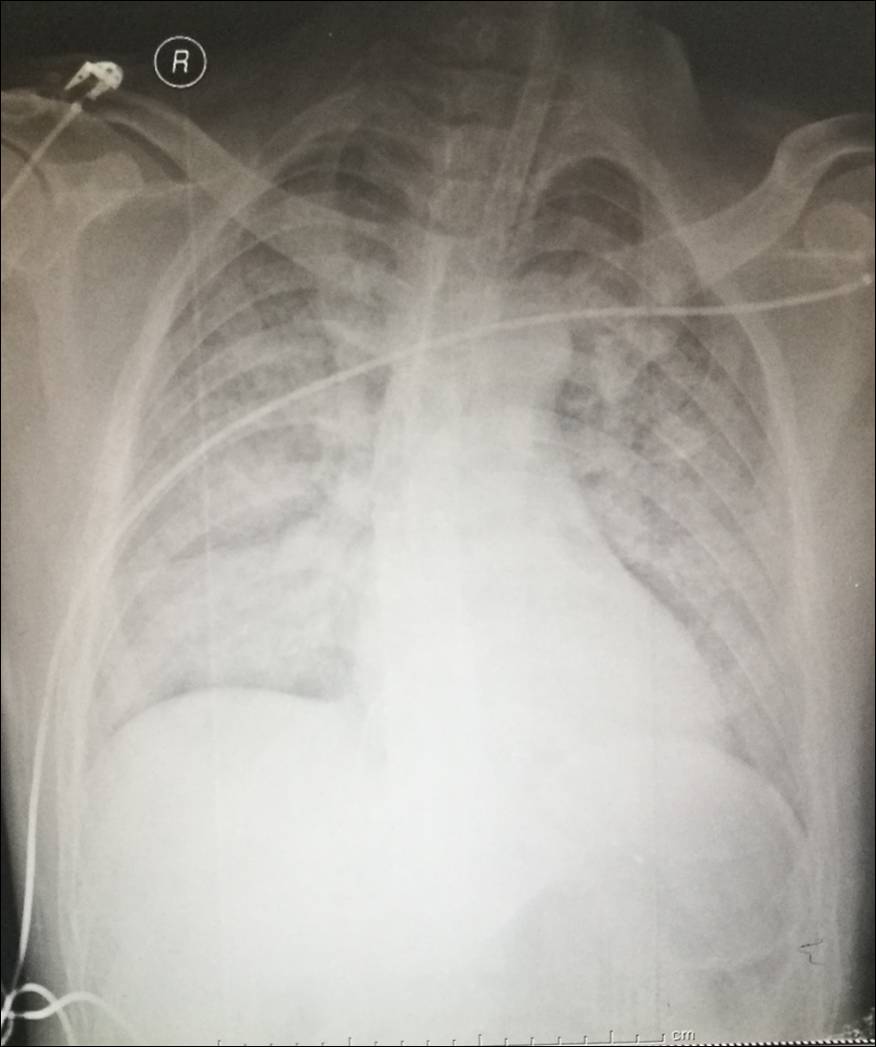

12-7 床边胸片

床边胸片(入院当天)